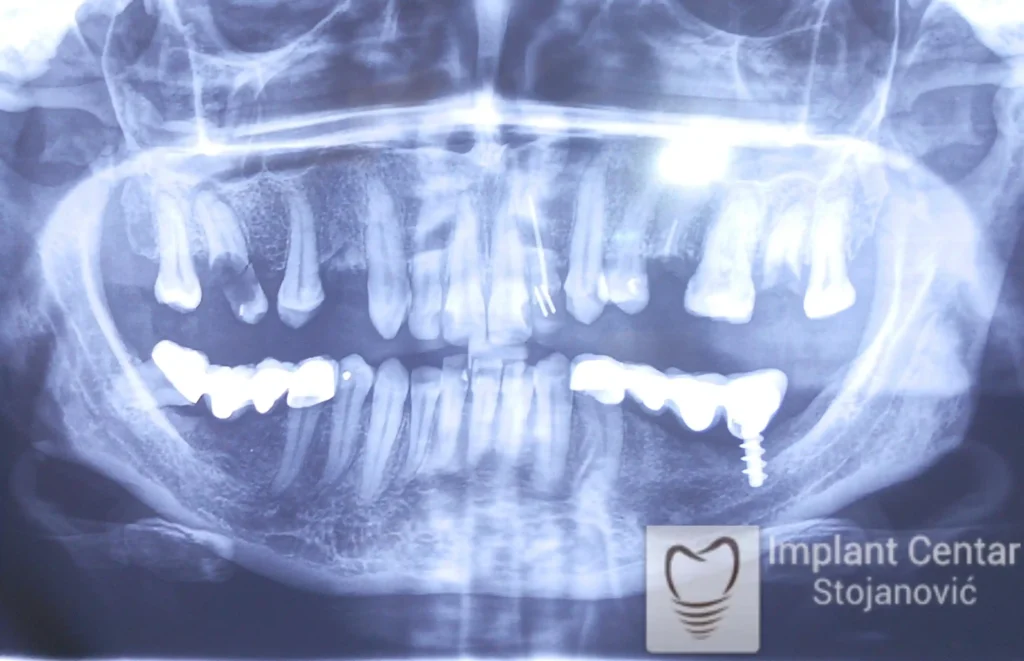

Na slici 1. slici 2. vidi se početno stanje — pacijent je imao prirodne zube, ali samo izradom novih mostova nije bilo moguće postići normalan odnos gornjih i donjih zuba (eugnatan zagrižaj).

Zbog toga je plan terapije uključivao vađenje svih preostalih zuba i ugradnju implantata u gornjoj i donjoj vilici. U gornjoj vilici postavljena su i dva tuberopterigoidna implantata, kao zamena za sinus lift proceduru, što se može videti na ortopan snimku nurađenom odmah nakon ugradnje (slika 3).